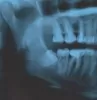

У меня рос зуб мудрости криво, но меня это не беспокоило, пока он не начал крошится и болеть в той области. Пошла к зубному хирургу, чтобы его выдрал. Но у него это не получилось, не смотря на то, что перепробовал все щипцы и даже молоток. Весь зуб разломал, остался только корень, сказал очень крепко сидит. И отправляет в другую клинику, чтобы мне его вырезали с костью! Неужели другого варианта нет??Сейчас жду пока спадет отек и заживет губа, а то мне рот не открыть широко и думаю там все равно ничего не видно пока. Что мне делать дальше???

P.S. Фото не мое, но очень похоже